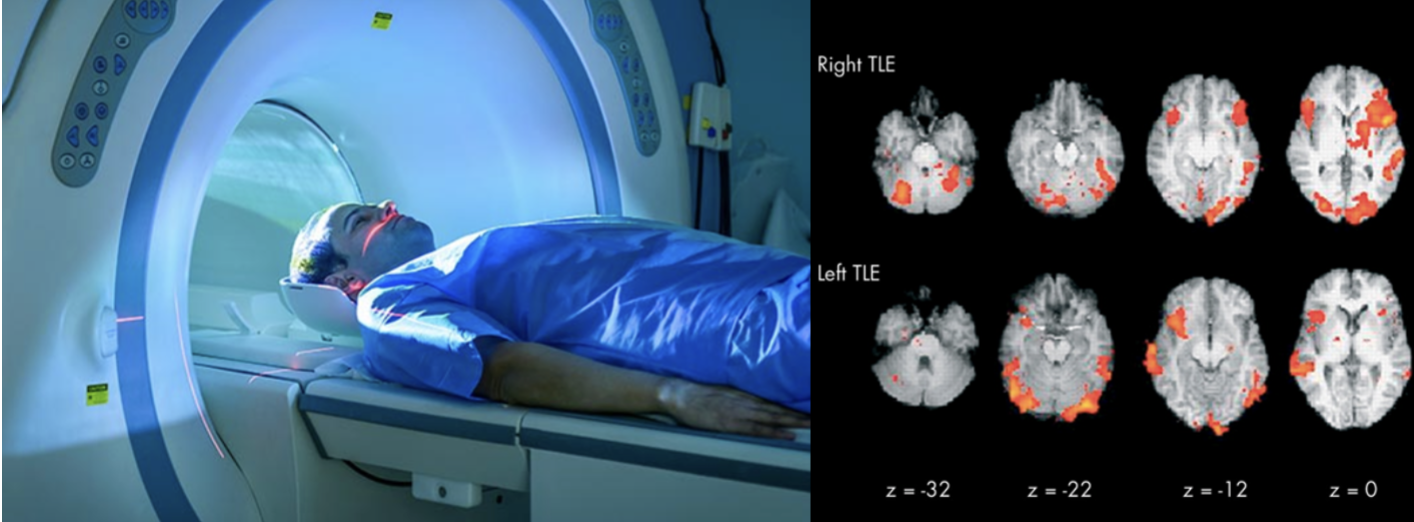

Functional Magnetic Resonance Imaging (fMRI)

detects changes in blood flow and oxygenation levels in the brain, which are associated with neuronal activity.

It provides detailed images of brain activity over time.